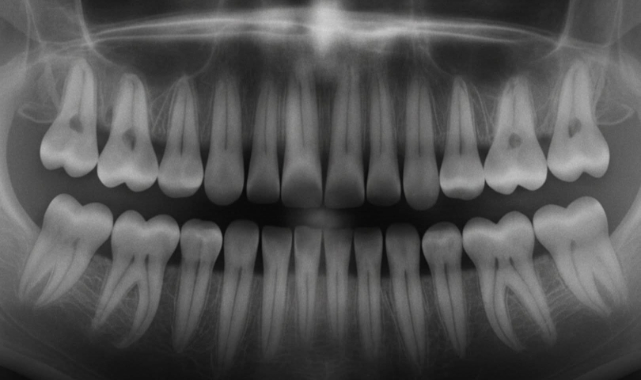

Japonya’da bilim insanları, diş kaybı ve çürük sorunlarına devrim niteliğinde bir çözüm sunabilecek yeni bir ilaç üzerinde çalışıyor. Deneme aşamasındaki bu tedavi, insan dişlerinin yeniden büyümesini teşvik ederek protez ve implantlara olan ihtiyacı ortadan kaldırmayı hedefliyor.

Erken çalışmalar, ilacın doğal diş rejenerasyonunu desteklediğini ve milyonlarca kişinin diş kaybı veya çürük sorunlarından kurtulmasına umut verdiğini gösteriyor. Geleneksel diş tedavilerinin aksine, bu yaklaşım vücudun kendi iyileşme mekanizmalarıyla çalışıyor, invaziv işlemleri ve sürekli bakım gereksinimini azaltıyor.Uzmanlar, tedavinin başarıyla uygulanması halinde ağız sağlığında devrim yaratabileceğini ve diş kaybını geçmişte bırakabileceğini belirtiyor. Diş eksikliği yaşayanlar için bu yenilik, sadece heyecan verici değil, hayat değiştiren bir gelişme olarak değerlendiriliyor. Japonya’nın öncülüğünde yapılan bu çalışmalar, diş hekimliği ve insan sağlığı alanında yeni bir dönemin kapılarını aralıyor.